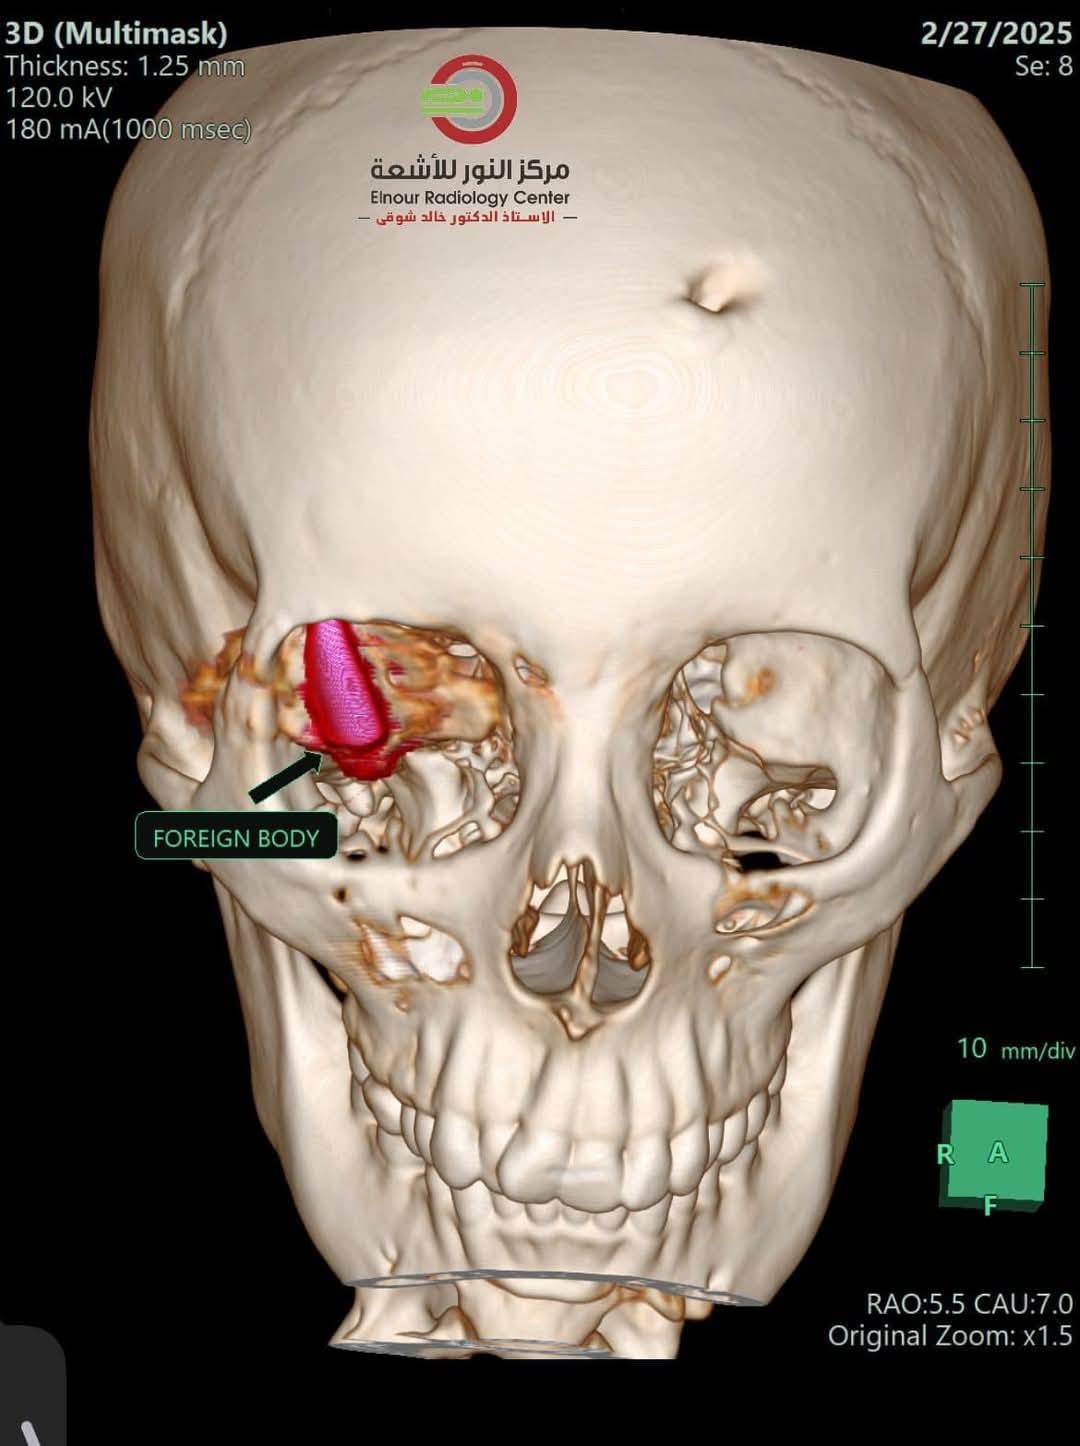

وكانت الشابة الفلسطينية قد تعرضت لإصابة بالغة نتيجة إصابتها بطلقة نارية اخترقت جمجمتها واستقرت خلف العين في منطقة حساسة، حيث تم إطلاقها من طائرة "كواد كابتر" خلال النزوح الذي تعرضت له في منطقة النصيرات.

ووصف الأطباء المصريون، العملية بأنها "بالغة التعقيد، حيث كان الطلق الناري قد استقر في منطقة حساسة داخل الجمجمة، مما كان يشكل تهديداً كبيراً على حياة المريضة".

وضم الفريق الطبي، مجموعة من الأطباء المتخصصين، عمل على مدار ساعات طويلة لضمان نجاح العملية، وسط ظروف صعبة ومعقدة. كما أشاروا إلى أن نجاح العملية كان بمثابة معجزة طبية نظراً للتحديات الكبيرة التي صاحبتها.